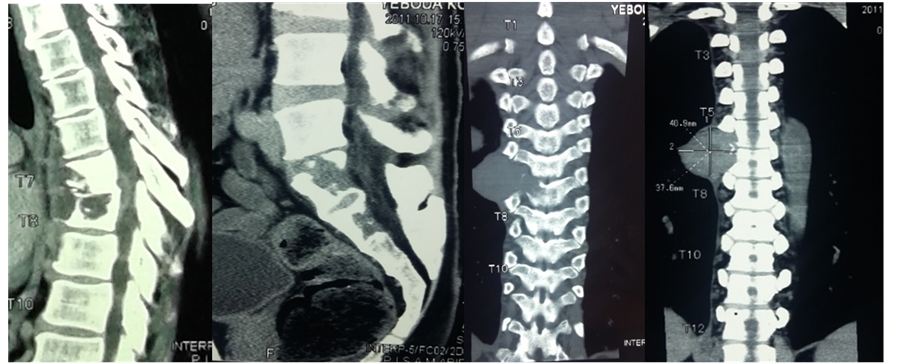

Mr. YKK, a 39-year-old ivorian, HIV immunocompetent and no other medical history, presented in February 2011 with progressive deterioration of his general health, thoracic rachialgia and intercostal pain, low back pain and lower limbs heaviness. Clinical examination revealed a slow thoracic spinal cord compression syndrome with a slight deficit and a 4/5 muscle strength of the lower limbs, a lumbosacral spine syndrome. CT scan and MRI of the thoracic spine showed lysis of T4, T5, T6 and T7 vertebrae, an epiduritis and paravertebral abscesses (Figure 1). CT scan of the lumbar spine demonstrated osteolysis of the left iliac wing with skin invasion. This lesion invaded the sacrum and the body of L5 (Figure 1). MRI of the lumbar spine showed no nerve root compression (Figure 1). Several diagnosis hypotheses were suggested: a multifocal tuberculosis (vertebral and iliac) or infection with other microorganisms (bacterial or parasitic), vertebral and iliac metastasis. A thoraco-abdo- minopelvic CT scan to search for a primary cancer was non-conclusive. An iliac bone biopsy performed revealed a giant cell granulomatous tissue, with large ovoid yeast consistent with Histoplasma duboisii. Histopathological examination of osseous biopsy concluded bone histoplasmosis with multiple localization of Histoplasma duboisii. The patient was treated with ketoconazole 400 mg daily for six months. Spinal decompressive surgery was not performed. Our conservative approach was based on clinical grounds of minimal neurological disorders and normal spine morphology. Following antifungal treatment the patient had satisfying clinical and radiological outcome. After three years follow-up, the clinical course was uneventful. The patient had neither symptoms of spinal cord compression nor signs of further localizations.

Figure 1. Sagittal view of thoracic CT scan showing osteolytic lesion T4, T5, T6 and T7 vertebral (a) at the sacrum, (b) thoracic frontal view (T5 to T7) lumbar frontal view osteolyic lesion and abcess (e) axial view with osteolytic in vertebral extending to pleural (f), axial view ilac osteolytic lesion (g) T1 weighted sagittal view showing spinal cord compression associated to vertebral body lesion (h) T2 weighed MRI on sagittal view, showing T4 - T7 epiduritis and paravertebral abscesses which is hyposignal (i) and (j). Histological examination showing Histoplasma duboisii in giant cell (Schiff periodic acid coloration ×100 (k).